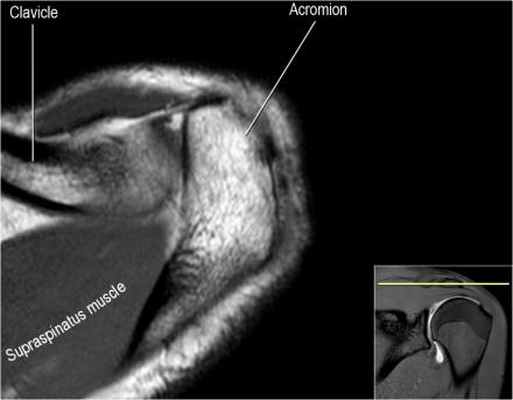

Нормальная анатомия плечевого сустава в аксиальных изображениях и контрольный список.

- поищите os acromiale, акромиальную кость (добавочная кость, расположенная у акромиона)

- обратите внимание что ход сухожилия надостной мышцы параллелен оси мышцы (это не всегда так)

- обратите внимание что ход сухожилия длинной головки двуглавой мышцы в области прикрепления направлен на 12 часов. Область прикрепления может быть различной ширины.

- обратите внимание на верхние отделы суставной губы и прикрепление верхней плече-лопаточной связки. На данном уровне ищется SLAP-повреждение (Superior Labrum Anterior to Posterior) и варианты строения в виде отверстия под сутавной губой (sublabral foramen - подгубное отверстие). На этом же уровне по задне-боковой поверхности головки плечевой кости визуализируются повреждение Хилл-Сакса.

- волокна сухожилия подлопаточной мышцы, создавая бицепитальную борозду, удерживают сухожилие длинной головки двуглавой мышцы. Изучите хрящи.

- уровень средней плече-лопаточной связки и передних отделов суставной губы. Поищите комплекс Буффорда. Изучите хрящи.

- вогнутость заднебокового края головки плечевой кости не следует путать с повреждением Хилл-Сакса, поскольку это нормальная форма для данного уровня. Повреждение Хилл-Сакса визуализируется только на уровне клювовидного отростка. В предних отделах мы сейчас на урвоне 3-6 часов. Здесь визуализируются повреждение Банкарта и его варианты.

- обратите внимание на волокна нижней плече-лопаточной связки. На данном уровне так же ищется повреждение Банкарта.